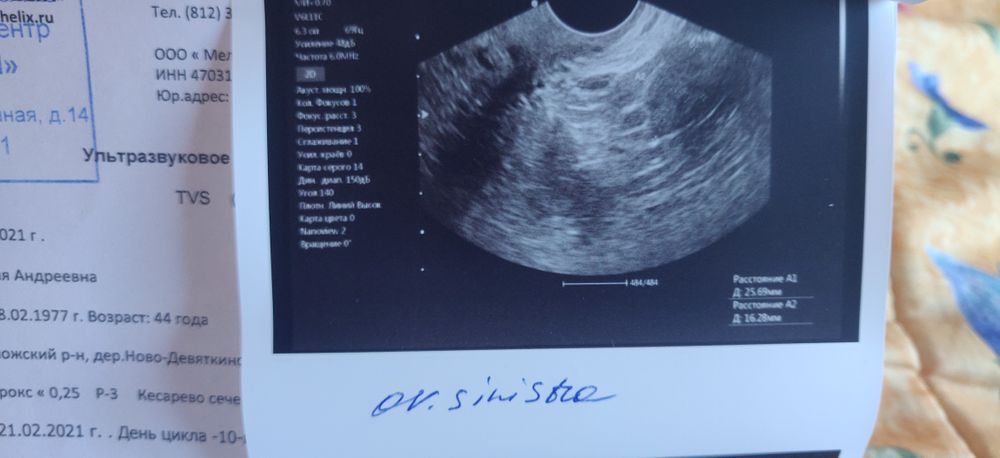

ФолликулометрияСитуация такая, в прошлом цикле была бб. Потом М, сегодня 10 ДЦ. Решила сходить на ФМ, посмотреть, что там происходит.

В общем, сказала она, что если регрессирующее жт и овуляции в этом цикле не ждать.

Прикладываю - тест на О сегодня, УЗИ и тест на беременность тоже сегодня (с прошлого цикла полосатят ещё).